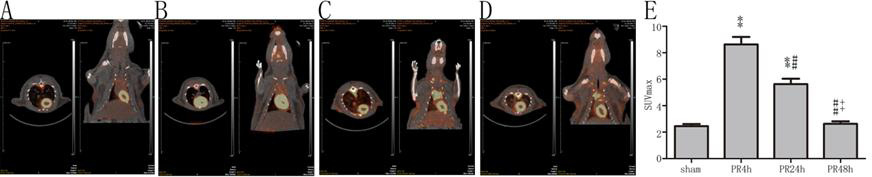

PR 4 h及PR 24 h组大鼠心肌SUVmax较sham组均显著升高(均P < 0.01,图 2),PR 24 h组低于PR 4 h组(P < 0.01),PR 48 h组与sham组比较差异无统计学意义(P > 0.05)。

| A:sham组(n=6);B:PR 4 h组(n=9);C:PR 24 h组(n=9);D:PR 48 h组(n=7);E:SUVmax的比较;与sham组比较,aP < 0.01;与PR 4 h组比较,bP < 0.01;与PR 24 h组比较,cP < 0.01 图 2 各组大鼠心肌葡萄糖代谢 Figure 2 Myocardial glucose metabolism of rats in each group |

生理情况下,心肌能量主要来自脂肪酸和葡萄糖代谢,受损心肌脂肪酸代谢下降,而葡萄糖代谢明显增强[16]。Mcnulty等[17]在心肌缺血模型中发现受损心肌葡萄糖代谢为正常心肌的6.6倍;有研究者认为受损心肌对葡萄糖的偏爱是因为葡萄糖产能耗氧更少[18];也有研究者认为葡萄糖酵解增强、产生的能量用以促进内质网对钙的转移、减轻钙超载[19]。本研究的CA模型中,ROSC 4 h心肌葡萄糖代谢为正常心肌5倍,而在48 h时已降至正常水平,ROSC后心肌葡萄糖代谢增强可能是心肌代谢受损、能量产生障碍的代偿反应。